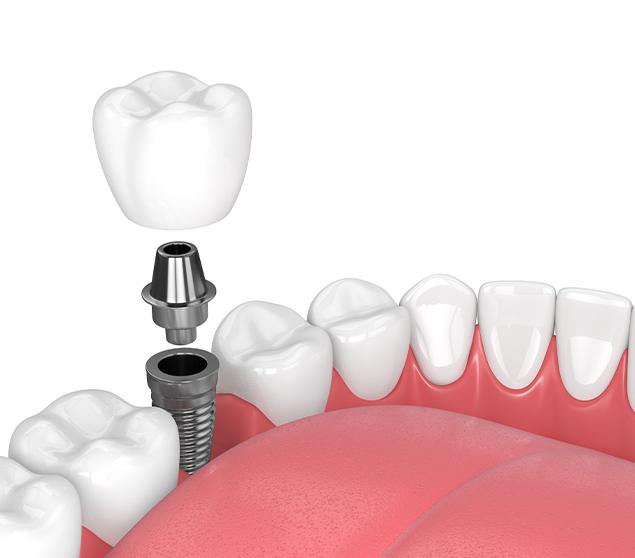

Dental implant treatment involves several steps, including planning, placement, healing, and restoration. The process and timeline vary depending on individual factors such as bone health and the number of teeth involved.